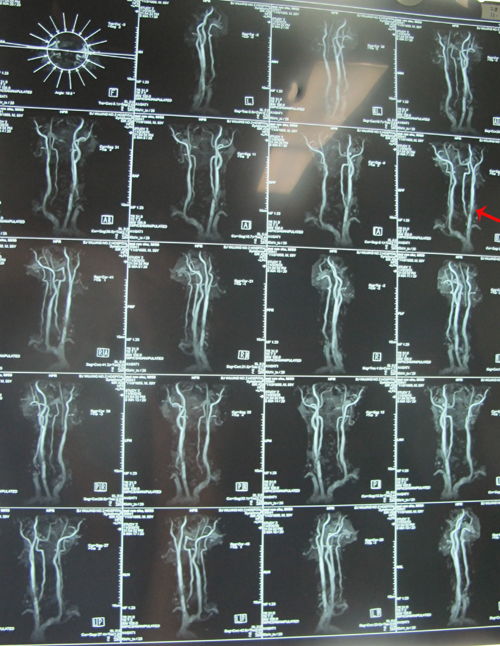

颈动脉超声检查:双侧颈动脉内膜增厚伴斑块形成(多发);右侧颈动脉球部狭窄(90%-99%,狭窄以远管腔纤细);左侧颈动脉球部狭窄(50%-69%);左侧椎动脉Ⅴ1段狭窄(50%-69%);左侧椎动脉开口处走行弯曲;右侧锁骨下动脉斑块形成(单发)。

TCD:双侧颈内动脉颅外段病变;前交通支开放;右颈内-外动脉侧枝开放;右侧大脑前动脉狭窄(重度)。

颅脑MRA:颅内动脉粥样硬化性改变;右侧海绵窦段、前床突上段、大脑中动脉狭窄

颈部MRA:右侧颈内动脉颈段较对侧明显纤细。